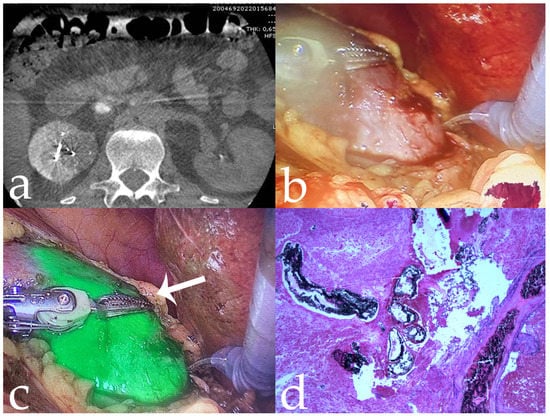

Figure 2. Same case as Figure 1. (a,b) Intra-operative tumor visualization before and after fluorescence imaging (arrows); (c) complete robotic-assisted tumor enucleation fluorescence imaging; (d) histological specimen confirming intralesional penetration of 18-Onyx (10×).

Administration of the embolizing agent allows the surgical procedure to be performed without renal pedicle clamping, thus causing no suffering to the renal parenchyma and allowing excellent renal function post-procedure. The high intra-lesional penetration is proved by the presence of the ICG-Onyx-18 mixture in the renal tumor vascular supply; the entity of the embolization performance is strictly connected with the dimension and the number of the renal tumor supply branches mapped on the pathology specimen as showed in Figure 2d, Figure 3e, Figure 5c and Figure 7d. In our study, no statistically significant differences were demonstrated between serum creatinine levels before and after the embolization procedure. In addition, the embolizing agent injected in stop-flow mode by balloon microcatheter, minimizing non-target embolization and promoting drug penetration, allowed excellent control of hemostasis; this resulted in a significant reduction in intra-procedural blood loss, with a median blood loss in our study of approximately 145 cc (range: 10–300 cc), which is slightly lower than the 250 cc reported by Simone et al. [16]. Furthermore, only one patient (1/13, 7%) had postoperative surgical complications.